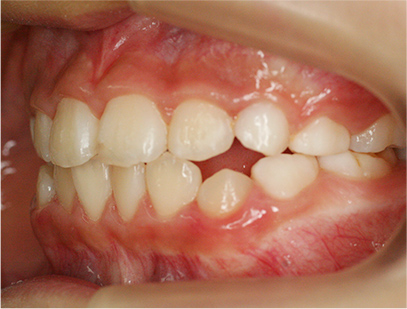

前歯部の開咬とデコボコ

前歯部が咬んでいないことを主訴として来院されました。精査、診断の結果「前歯部にデコボコを伴う開咬」と診断されました。

下の歯の裏側に舌が出ないように矯正装置を取り付け、そして上の歯には取り外しのできる矯正装置を装着して、側方に拡大を行います。

取り外しのできる矯正装置、舌が出せなくなる矯正装置(フェンス)

• 右側

• 左側